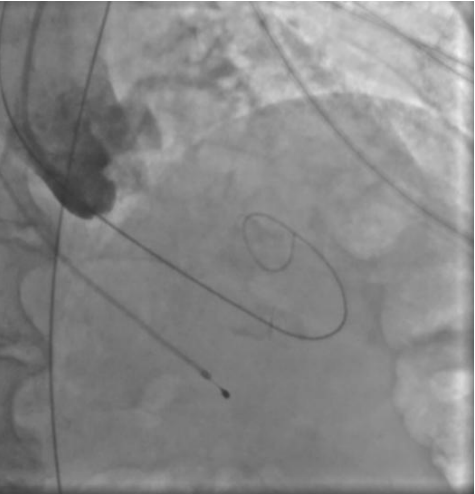

Рис. 3. Пациентка Б. Ангиография корня аорты: визуализируется минимальная регургитация.

Рис. 4. Пациентка Б. Прямая имплантация протеза.

Рис. 5. Пациентка Б. Контрольная аортография.

Процедура ТИАК выполнялась по стандартной методике, принятой в нашем центре, за исключением этапа предилатации, который был сознательно пропущен с целью предотвращения развития тяжелой аортальной регургитации (рис. 3-5). Были выполнены позиционирование и прямая имплантация биологического клапана "ACURATE Neo 2" 23 мм, впоследствии дополненная постдилатацией баллонным катетером "Valver" 20×40 мм. На контрольной аортографии: аортальная регургитация 0-1 степени. Коронарные артерии не скомпрометированы, коронарный кровоток удовлетворительный. После выполнения основного этапа операции интродьюсер из правой общей бедренной артерии удален, затем выполнено ушивание места доступа системой зашивающего устройства "ProGlide" (6F) и AngioSeal VIP (8F), наложен кожный шов. Интраоперационно и ранний послеоперационный период протекал без особенностей.

Во втором клиническом случае был учтен предыдущий опыт и изменена тактика проведения вмешательства у пациентки с аналогичным фенотипом ЛЖ. Исключение этапа баллонной вальвулопластики способствовало снижению риска перегрузки ЛЖ за счет аортальной регургитации. Таким образом, на всех этапах операции у второй пациентки сохранялась разграничительная функция нативного клапана или биопротеза. В третьем клиническом случае у пациентки наблюдался массивный кальциноз АК, что не позволяло исключить этап предилатации. Поэтому было принято решение выполнить щадящую вальвулопластику для обеспечения технической возможности проведения через АК системы доставки протеза. Тем не менее даже умеренная регургитация, появившаяся после этапа предилатации, негативно повлияла на гемодинамику пациентки, которая была скорректирована лишь после имплантации биопротеза. Таким образом, у пациентки удалось избежать выраженной объемной перегрузки ЛЖ, благодаря чему удалось успешно выполнить вмешательство, не прибегая к СЛР.